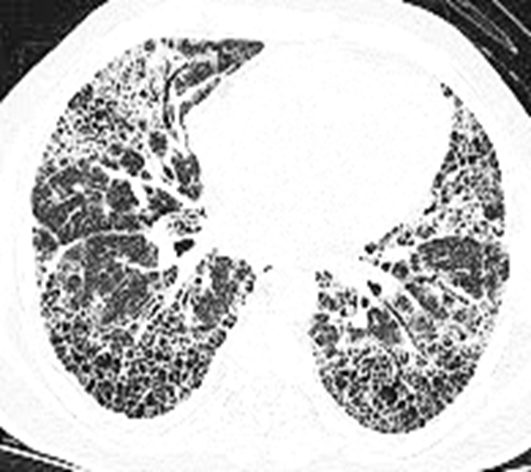

Key HRCT features of UIP:

• Subpleural and basal predominance

• Reticular opacities (network-like lines)

• Honeycombing: clustered cystic airspaces, 3–10 mm in size

• Traction bronchiectasis: dilated airways pulled by fibrotic tissue

• Absence of features suggesting alternative diagnoses (e.g., extensive ground-glass opacities, nodules, consolidation, or upper-lobe predominance)

Imaging (HRCT)

UIP pattern: basal/subpleural reticulation, honeycombing, traction bronchiectasis

Rapidly progressive fibrosing interstitial lung disease. Marked subpleural and bilateral basal traction bronchiectasis, honeycombing, and irregular reticular opacities suggest an atypical UIP pattern/idiopathic pulmonary fibrosis.

Imaging Features

IPF is radiologically defined by a usual interstitial pneumonia (UIP) pattern in the absence of a known cause. High-resolution computed tomography (HRCT) typically reveals subpleural and posterior basal predominance of honeycombing, reticular septal thickening, and traction bronchiectasis. These findings are characteristic of UIP and support the diagnosis of IPF.